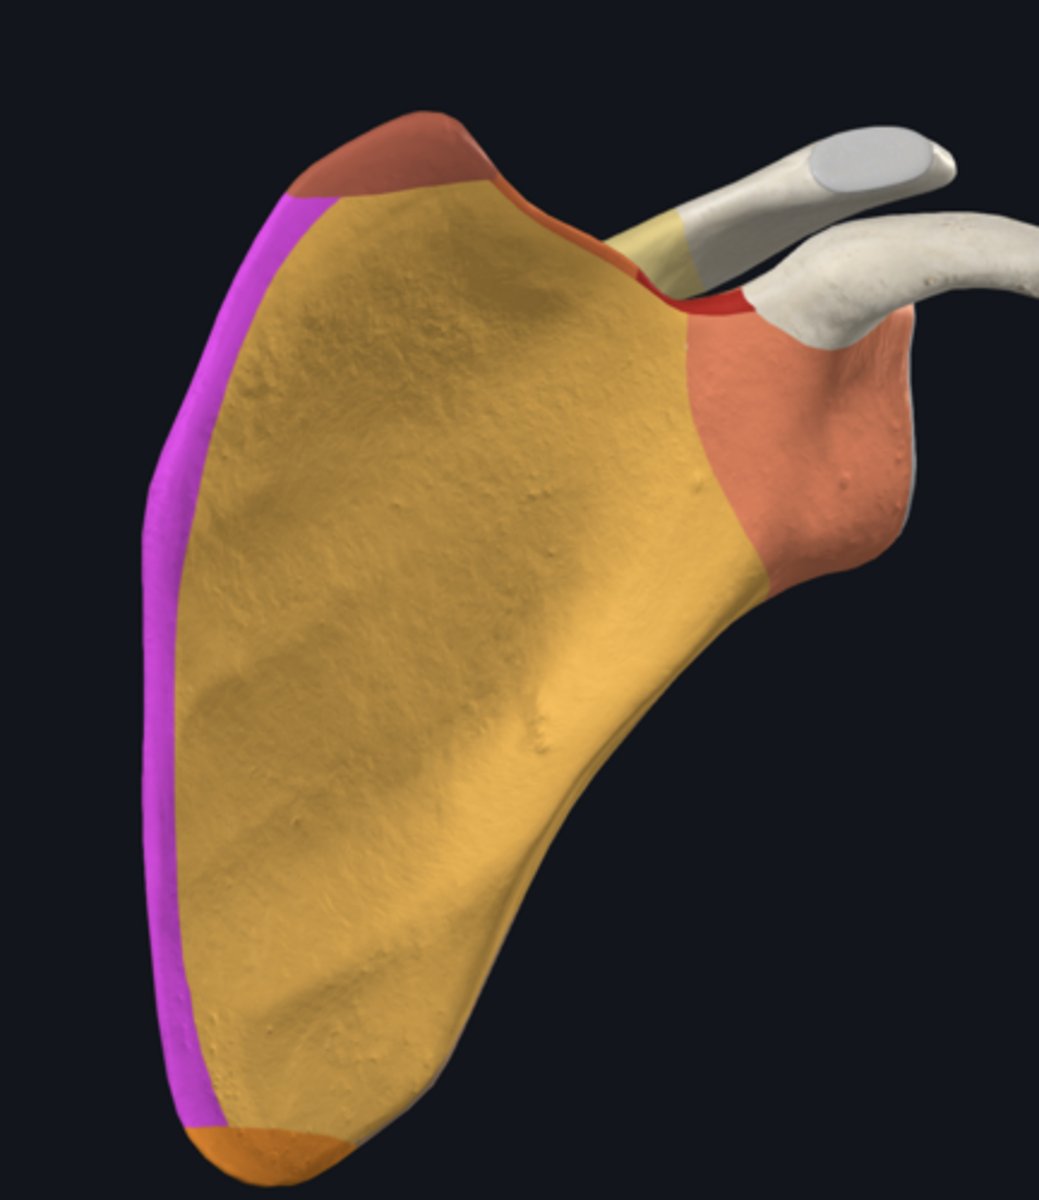

Acromion

Superior angle of scapula

Coracoid process

lateral border of scapula

medial border of scapula

inferior angle of scapula

body of scapula

Head of scapula

neck of scapula

costal surface of scapula

lateral angle of scapula

posterior surface of scapula

scapular notch

superior border of scapula

acromial angle

clavicular facet

glenoid fossa

infraglenoid tubercle

infraspinous fossa

spine of scapula

supraglenoid notch

subscapular fossa

supraglenoid tubercle

supraspinous fossa